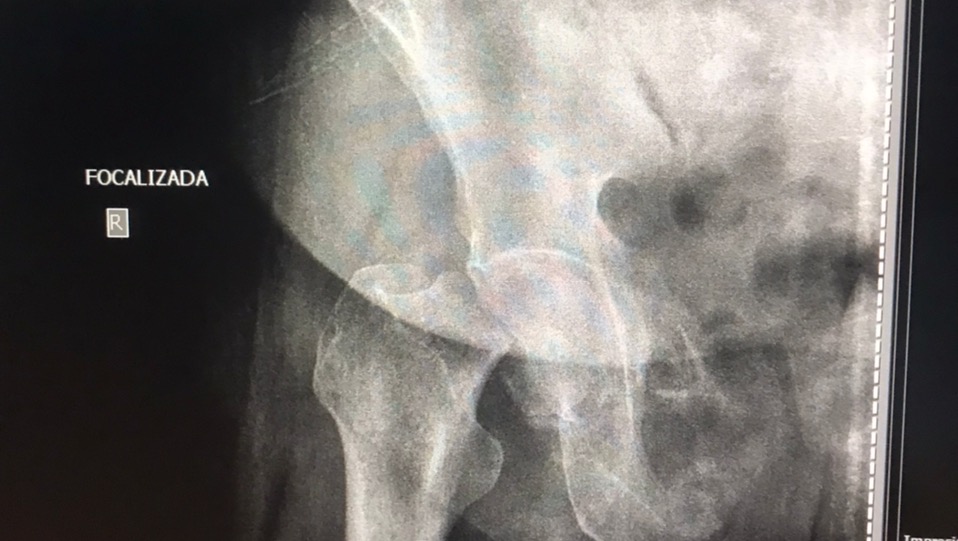

El motivo de esta campaña es para ayudar a la mamá de mi mejor amiga (Maria Alejandra Cáceres). Su mamá, la señora Ida Rincón, el 15 de diciembre, se presentó en la consulta de un traumatólogo en la ciudad de Maracaibo, por presentar un fuerte dolor en la entre pierna. Sorpresa para sus familiares cuando los resultados de los rayos X mostraron una fractura en la cabeza del fémur, y la única forma de solventar el problema es con una prótesis de cadera total derecha.